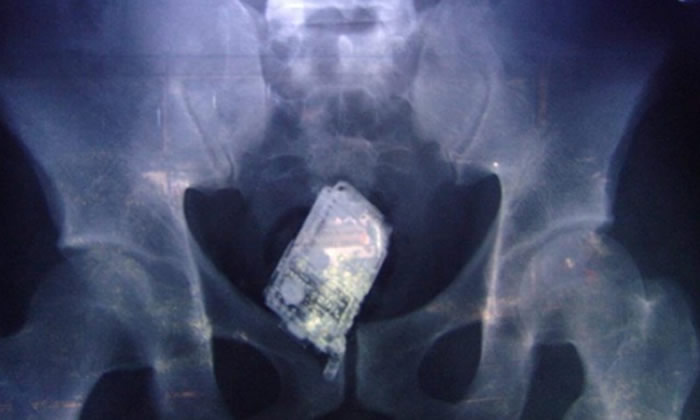

Después de someterlo a un examen de rayos X en el que se constató que tenía los tres aparatos en su estómago, los médicos le recetaron laxantes y lo devolvieron a prisión pero no logró expulsarlos y lo que fue conducido a un hospital para ser sometido a una operación.

Dos de los reos guardaban los teléfonos en el recto: uno tenía cuatro microaparatos y el otro cinco. El tercer preso fue descubierto al pasar por los rayos X con diez minicelulares con auriculares en su estómago y fue sometido a una operación para retirarle todos los aparatos. (ECHA- Agencias)